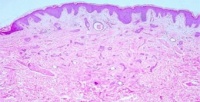

认为汗管瘤是由脂肪代谢障碍所引起的人体表皮小汗腺导管的一种痣样肿瘤,与内分泌、妊娠、月经及家族遗传等因素有关。切片显微镜下症征为真皮上部可见多数管埋入纤维基质中,导管内衬两层上皮细胞,腔内含有无定形碎片。部分导管为小的上皮细胞索构成逗点状或蝌蚪状外观。